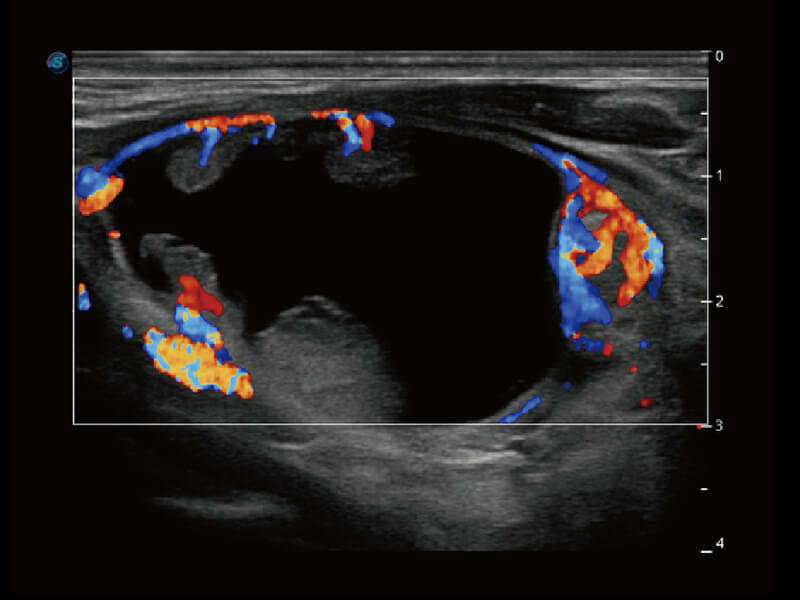

S60创新的探头工艺、高精度模数转换系统、前沿的波束重建技术,从前端信号处理每一个环节采集无损声学数据,真实还原组织原貌,再现解剖细节。